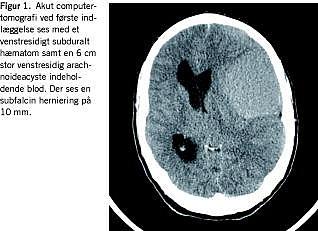

To timer efter operationen var patienten vågen, og ptosen var svundet. I løbet af de følgende tre dage svandt den ekspressive afasi. Ved udskrivelsen til hjemmet på sjette dag var han neurologisk intakt og i øvrigt velbefindende. På tiende dag blev han igen indlagt under samme billede. Fornyet computertomografi viste gendannet cyste. Efter reoperation og klinisk kontrol inklusive computertomografi tre måneder senere (Figur 2 ) var han velbefindende og uden mén.